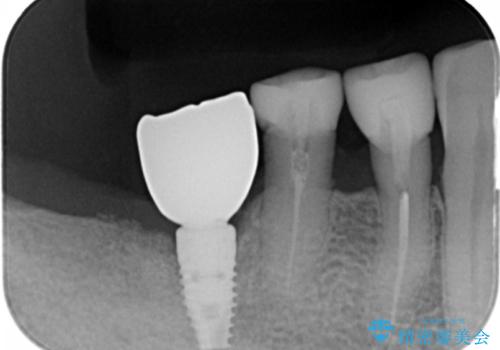

奥歯のインプラント 70代男性

- 70代男性

- 奥歯の違和感を主訴に来院された患者様です。

精査したところ、右下の奥歯は大きなう蝕により保存不可能な状態でした。

患者様のご希望により、抜歯後インプラント治療を行いました。

- ¥550,000 (インプラント、骨増生、アバットメント、クラウン) ※税込費用は治療当時の料金となります

奥歯でしっかりと咬むことができるようになり、大変喜んで頂けました。

クラウンの種類:オールセラミッククラウン スタンダード